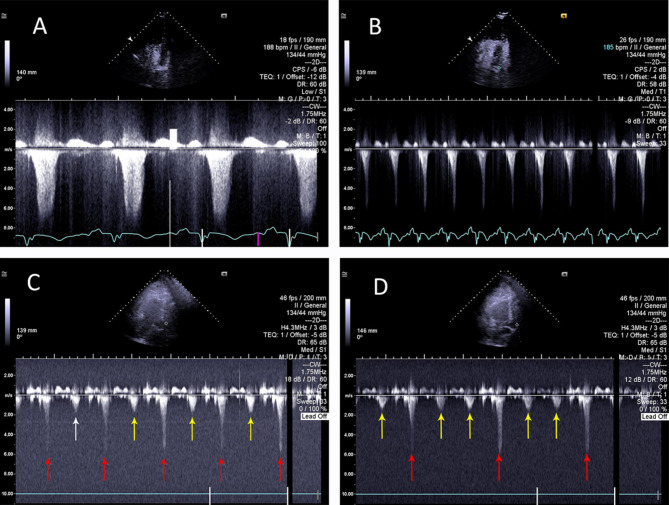

Case presentation: An 88-yo man presented with angiotensin converting enzyme inhibitor (ACEI) - induced angioedema. He received steroids and adrenaline, but progressed to the respiratory arrest, requiring emergency awake fiberoptic intubation and mechanical ventilation. Echocardiography revealed catecholamine-induced reversed Takotsubo cardiomyopathy. The patient suffered asystolic cardiac arrest on arrival to intensive care unit (ICU), requiring cardiopulmonary resuscitation (CPR). Bradycardia and hypotension were treated with atrial pacing and (IABP). Icatibant was administered for angioedema. After several hours of haemodynamic stability, severe hypotension returned. Bedside echocardiographic diagnosis of recovery from Takotsubo and new development of IABP-induced dynamic left ventricular outflow tract obstruction (DLVOTO) was made. Stopping IABP resulted in rapid haemodynamic recovery. Repeated doses of Icatibant were needed. The patient survived and returned to independent living.

Conclusions: Immediate echocardiographic recognition of iatrogenic DLVOTO caused by IABP allows discontinuation of IABP support as a life-saving intervention. Dynamic application of spectral Doppler with changes in IABP settings is required for correct diagnosis.